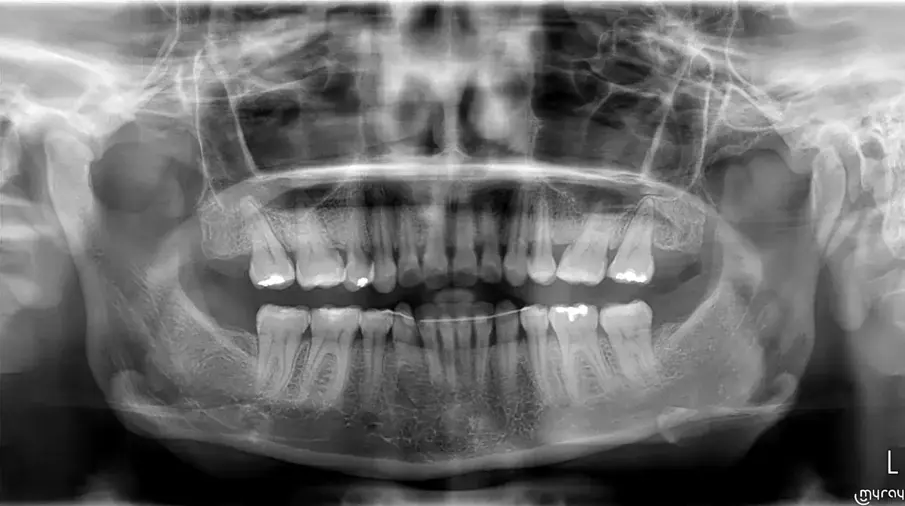

Фиг. 4а.

Първоначална цефалометрична рентгенография и панорамна дентална томография.

Фиг. 4b.

35-годишна пациентка постъпва със струпване на зъби, болки в мускулите и ставите и главоболие след събуждане. При прегледа се установява I скелетен клас със струпване и бимаксиларна протрузия. Изследването на лицето показа конвексен профил с изпъкнали устни и квадратна форма на лицето, която се засилва при усмивка (фиг. 1-4). Тя съобщава за бруксизъм и се наблюдава двустранна хипертрофия на масетерите, но няма изменения в темпоромандибуларните стави.